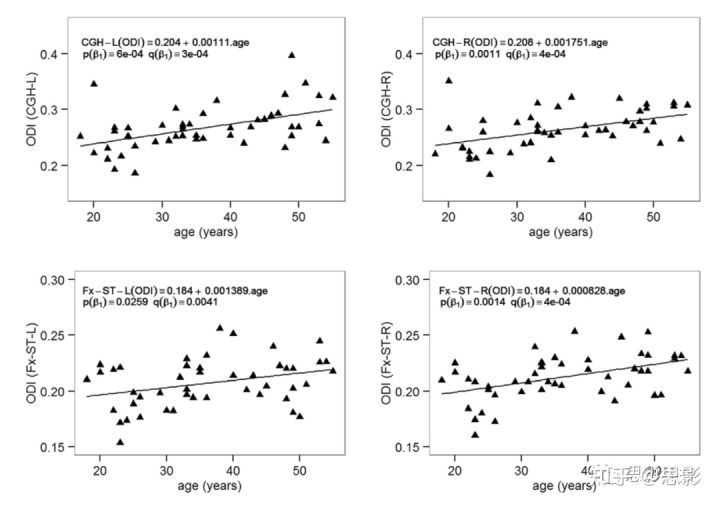

因为在回归模型1中,所有的扩散指标和ROI组合下β3都不显著,因此老化效应在两性中是一致的。因此,无论是回归模型2还是回归模型3的β1都被用来描述男女共同的老化效应。表3总结了白质ROI中那些显著的β1(斜率),图4显示了这些斜率每十年的变化百分比。图5为年龄相关的重要ROI中DTI和q空间分析的显著回归曲线。ODI的回归线如图6。DTI扩散指标随年龄变化的总体趋势是AD降低,RD增加,FA降低。MD在年龄上没有显著差异。同样,组织限制(P0)在大多数白质ROI中相对稳定,但在2个ROI中(包括钩状束,UNC)显著下降。与年龄相关的NODDI指标变化的总趋势是增加了纤维弥散度(ODI),其中显著的白质ROI发生率最高。轴突内体积分数(ICVF)稳定,所有白质ROI无显著变化。

图6 模型3中NODDI-ODI在年龄相关的关键ROIs中包括穹窿终纹(Fx-ST)和海马扣带回(CGH)的显著线性回归结果。

老化速率β1如表3。p值表示未校正的显著性水平,q值表示48个ROI的多重比较的错误发现率(false discovery rate,FDR)。Q<0.05被认为是显著的。